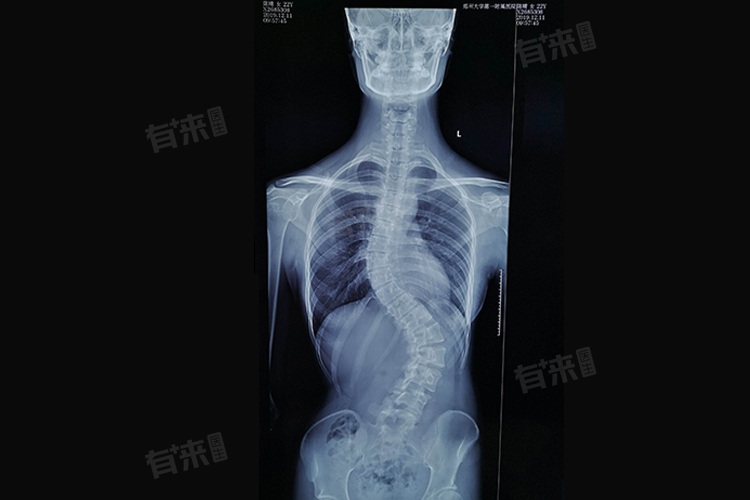

脊椎骨侧弯曲矫正手术费用因侧弯程度、手术方式及材料、医院级别和地区差异等因素而有所不同,一般在几万到几十万元。具体费用还需要根据患者的实际情况,在咨询医生和医院后确定。

脊椎侧弯的程度不同,手术的复杂程度和所需的医疗资源也会有所差异。轻度侧弯矫正相对简单,费用可能较低。而严重的侧弯,手术难度大,涉及的节段多,费用会相应增加。一般来说,轻度侧弯矫正手术费用可能在5万-8万元。